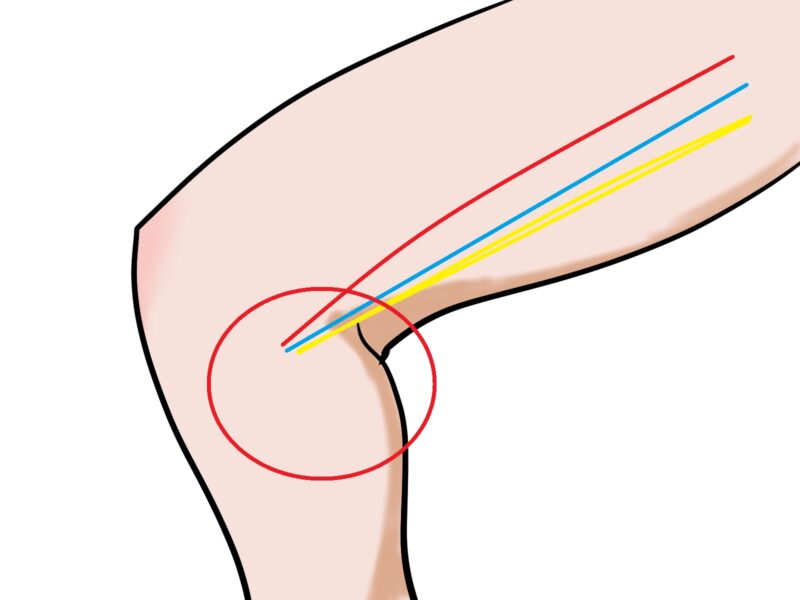

鵞足炎とは簡単に言うと膝の内側の腱や滑液包の炎症症状です。まず鵞足とは何と思われるかと思います。鵞足とは読んで字のごく「鵞=ガチョウの足」の事です。

痛みが出る場所が膝の下5センチから7センチほどの場所でそこには3本の筋肉がくっついています。縫工筋、半腱様筋、薄筋と言う筋肉です。これらのついている部分がちょうど鳥の足のような形に見える事から鵞足と呼ばれています。

膝の屈曲により筋肉の付着部に負担がかかり、腱同士が摩擦でこすれたり滑液包と言う関節にある軟部組織と骨のあいだにあるクッションのような場所が炎症を起こす事により発症します。